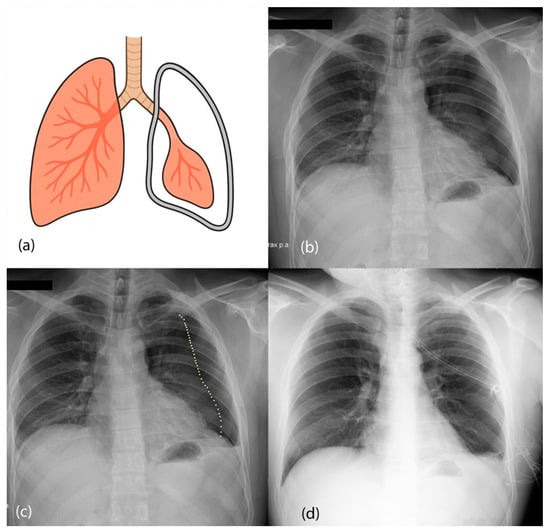

- Bintcliffe, O.; Maskell, N. Spontaneous pneumothorax. BMJ 2014, 348, g2928. [Google Scholar] [CrossRef] [PubMed]

- O’Connor, A.R.; Morgan, W.E. Radiological Review of Pneumothorax. BMJ 2005, 330, 1493–1497. [Google Scholar] [CrossRef]